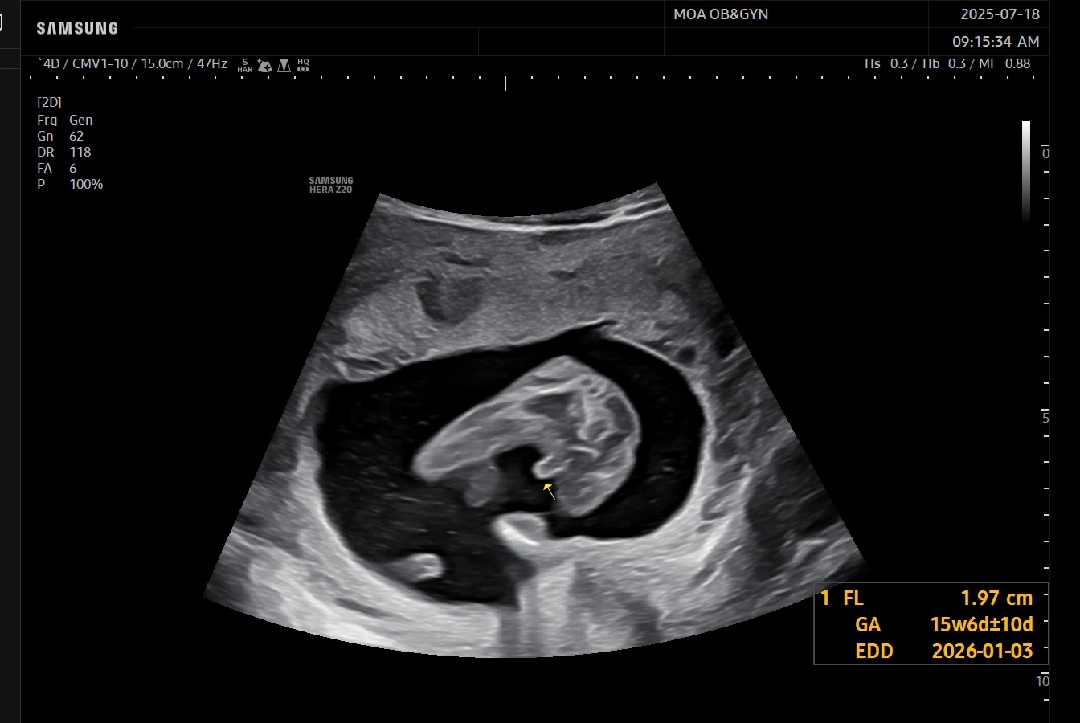

15주 4일 반전없이 아들 확정 🌶

14주까지만해도 기대햇건만 이건 더이상 반전은 힘들겠더라고요ᆢㅋㅋㅋ 가랭이 사이 대왕꼬츄 뙇!!!!🌶🌶 저는 아들맘 확정인걸로 😂